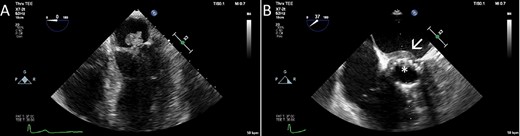

In October 2019, she was referred from the primary care physician due to a 3-week history of cough and fever chills and a C-reactive protein (CRP) of 128 mg/L (reference < 5 mg/L). A systolic murmur raised suspicion of infective endocarditis. The diagnosis was confirmed with transesophageal echocardiography (TEE), which in addition to mitral and prosthetic valve vegetations of up to 20 mm, also showed an abscess in the intervalvular fibrous body (Fig. 1). Blood cultures revealed growth of Cutibacterium spp. After a thorough discussion with the patient, the decision for surgery was taken.

The TEE showed a large vegetation on the native mitral valve (A), vegetations on the TAVI prosthesis (B, asterisk) and an abscess in the intervalvular fibrous body (B, arrow).